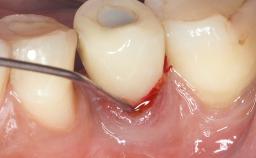

Late Presentation of Peri-Implant Mucositis Requiring Soft-Tissue Augmentation and Esthetic Crown Lengthening at Implant Site 11